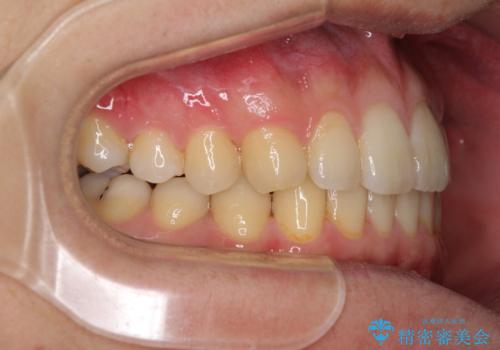

前歯のクロスバイトと抜歯が必要な奥歯の虫歯 インビザラインとインプラント治療

- 前歯のクロスバイトと、大学生のころから放置している虫歯を気にして来院された患者様です。

マウスピースでの矯正治療を希望されていましたが、前歯のクロスバイトは不十分な仕上がりや歯髄壊死などのリスクが高くなるため、術前にワイヤーで大まかに整えてからインビザラインにて矯正治療を行うこととしました。

奥歯の虫歯は抜歯が必要であったので、矯正治療前に抜歯をし、矯正治療と並行してインプラントによる補綴治療を行うこととしました。